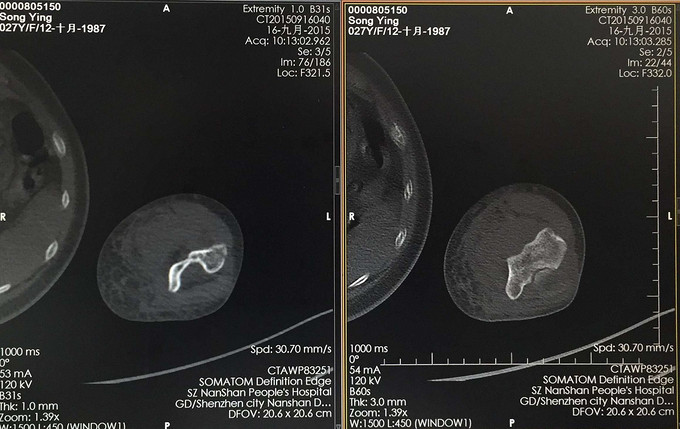

查体:患肢肿胀畸形,肘关节活动受限,感觉血运未见异常。 X线:右肱骨远端骨折 CT:右肱骨远端骨折,骨折线波及关节面

右肱骨远端骨折 行右肱骨远端骨折切开复位内固定术